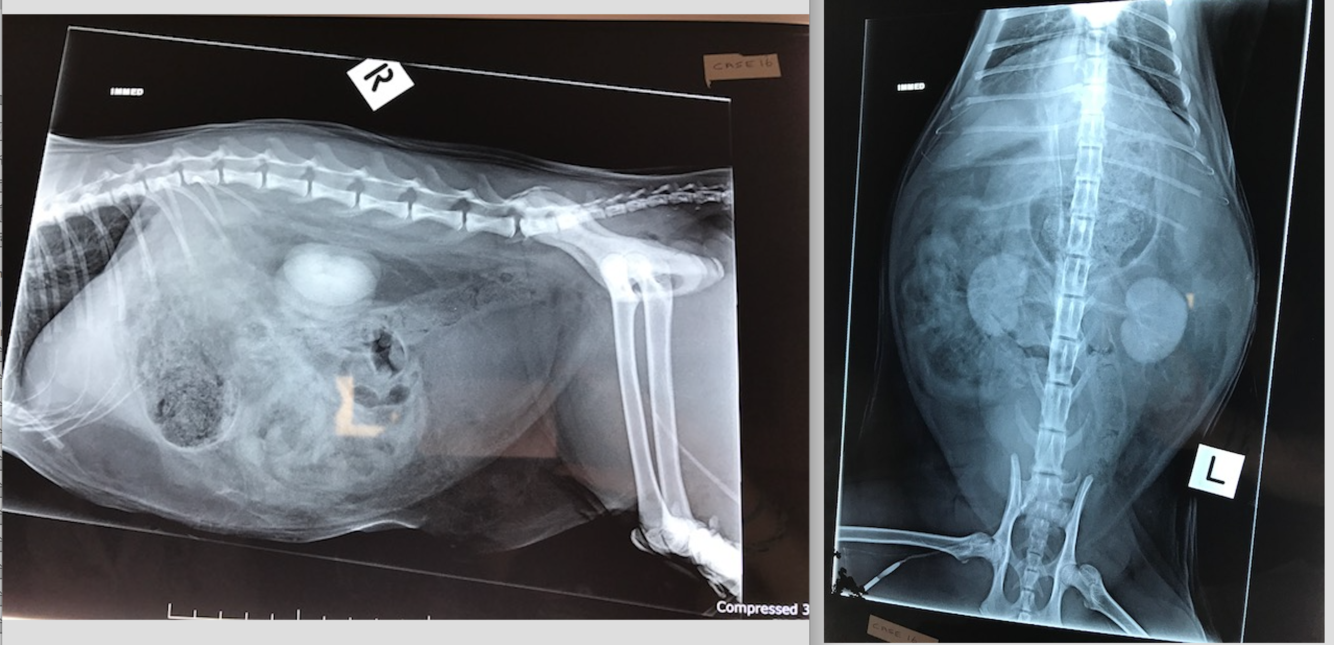

Oscar 12 yo MN DLH

Hx: Vocalised and collapsed at home

CE: Systolic heart murmur, increased RR. Pale gums, tense abdomen with mass lesion palpable cranially.

Large irregularly margined mass within the cranioventral abdomen– which is the most likely organ of origin for this mass?

The mineralised opacity caudal to this mass- what is it called?

2-3 x the length of L2 for cats.

2.5-3.5 the length of L2 for dogs.

Hepatocellular Carcinoma